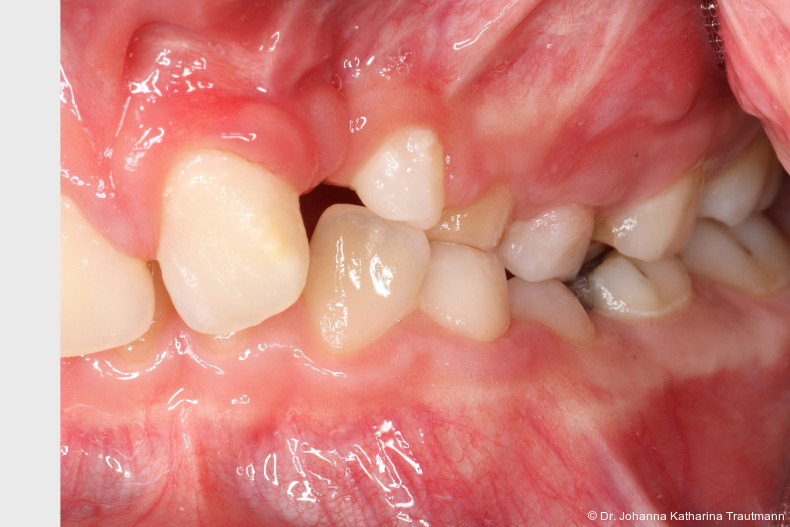

Auch im Rahmen der Zertifizierung durch das German Board of Orthodontics and Orofacial Orthopedics (GBO) wird dieser Aspekt gezielt hervorgehoben: Bewerberinnen und Bewerber sind aufgefordert, Fälle vorzustellen, die eine enge Kooperation verschiedener Fachdisziplinen dokumentieren und somit die Vielschichtigkeit und Tiefe der kieferorthopädischen Behandlungsmethoden aufzeigen. Hierdurch wird deutlich, dass die Kieferorthopädie sich nicht allein auf fachspezifische zahnmedizinische Themen fokussiert, sondern einen wesentlichen Beitrag zur allgemeinen interdisziplinären medizinischen Versorgung leistet. Der nachfolgende Fallbericht zu einem Patienten mit ein seitiger Lippen-Kiefer-GaumenSpalte zeigt exemplarisch, wie bei einem um fangreichen Behandlungs fall die Kieferorthopädie als zentrales Bindeglied zwischen den Disziplinen fungiert und damit maßgeblich zur funktionel len und ästhetischen Rehabilitation des Patienten beigetragen hat. Erstvorstellung Der Patient stellte sich im Alter von 11,5 Jahren auf Anraten einer niedergelassenen Kollegin in der Poliklinik für Kieferorthopädie der Universitätsmedizin Göttingen vor. Hauptanliegen war die Beurteilung einer möglichen Durch bruchsproblematik sowie die Indikationsstellung einer sekundären Osteoplastik im Rahmen einer einseitigen Lippen-Kiefer-Gaumen-Spalte.

Allgemeinanamnestisch berichtete der Patient über eine eingeschränkte Nasenatmung und nächtliches Schnarchen. Ein bestehendes Asthma bronchiale wurde medikamentös durch ein corticoides Bedarfsspray kontrolliert. Der CMD Kurzcheck nach Ahlers und Jakstat1 zeigte keine Auffälligkeiten. Extraoral fiel ein konvexes Profil mit ausgeprägter Kinnprominenz sowie enface der linksseitige Narbenzug mit charakteristisch abgeflachtem Nasenflügel auf.

Das Fernröntgenseitenbild zeigte eine skelettale Klasse IIAnomalie mit einem Wits von 5,6 mm, bei einer tiefen Konfiguration (ML NL = 16,5°) mit bialveolär retrudierten Fronten (OK1NA = 5,9°; UK1NB = 10,4°), was sich auch in der Modellanalyse widerspiegelte. Hier zeigte sich zudem ein schmaler Oberkiefer mit multiplen Kippungen und Rotationen in der Front, einem hypoplastischem 22 sowie einer Mesialwanderung des 16. Des Weiteren zeigte sich eine asymmetrische Bisslage mit 1 PB distal rechts und ½ PB distal links bei einem Overjet von 2,5 mm sowie einem Overbite von 5 mm. Während im Unterkiefer bereits die zweite Zahnwechsel phase begonnen hatte, zeigte sich im Oberkiefer noch kein Wechsel in den Stützzonen. Gerade bei Patienten mit Spaltbildungen ist eine engmaschige Überwachung des Durchbruchs der oberen Eckzähne essenziell. Während bei der Allgemeinbevölkerung die Prävalenz von verlagerten Eckzähnen bei ca. 2,8 Prozent liegt2, ist diese bei Patienten mit Lippen-Kiefer-Gaumen-Spalten um den Faktor 10 erhöht.3, 4 Als klassische Risikofaktoren gelten zudem Platzmangel, transversale Enge aber auch Fehlstellungen, Nichtanlagen oder Hypoplasien der zweiten Schneidezähne. Diese übernehmen normalerweise die Funktion der Leitschiene für den S-förmigen Durchbruch der Eckzähne. Im vorliegenden Patientenfall kommen also mehrere Risikofaktoren für eine Verlagerung zusammen, was die rechtzeitige Diagnostik zur Abklärung einer Durchbruchsproblematik rechtfertigt. Da im Spaltbereich auch zusätzlich ein ausgeprägtes Knochendefizit vorliegen könnte, sollte auch immer die Option einer sekundären Osteoplastik abgewogen werden, deren Indikation und Timing optimal zum Durchbruch der Canini angepasst werden sollte.5